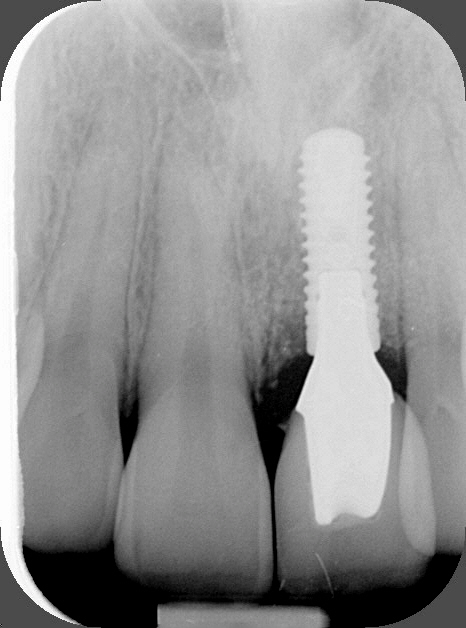

Radiographie implant + couronne céramique

Remplacement de la dent perdue par une couronne sur un implant